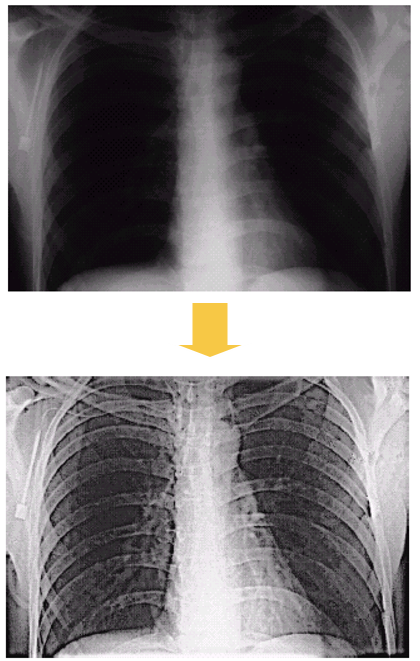

5.1 Image enhancement